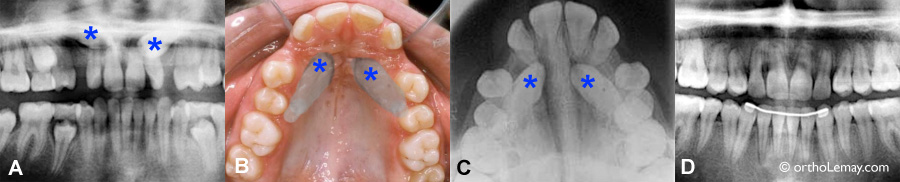

Amélioration significative de la position des canines supérieures permanentes

Amélioration significative de la position des canines supérieures permanentes (* rouge) après l’extraction sélective des canines temporaires (* bleu) et des premières molaires temporaires (* vert). Ces changements se sont produits en moins d,une année. Sans cette intervention, il y avait de fortes chances que les canines permanentes se soient dirigées vers le palais et deviennent sévèrement incluses.